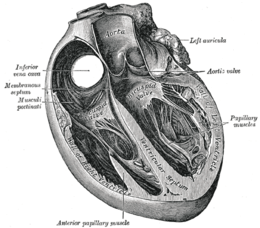

Section of the heart showing the ventricular septum. (Bicuspid valve visible at center.)

Section of the heart showing the ventricular septum. (Bicuspid valve visible at center.)

The inelastic chordae tendineae are attached at one end to the papillary muscles and at the other to the valve cusps. Papillary muscles are finger-like projections from the wall of the left ventricle. Chordae tendineae from each muscle are attached to both leaflets of the mitral valve. Thus, when the left ventricle contracts, the intraventricular pressure forces the valve to close, while the tendons keep the leaflets coapting together and prevent the valve from opening in the wrong direction (thus preventing blood to flow back to the left atrium). Each chord has a different thickness. The thinnest ones are attached to the free leaflet margin, whereas thickest ones (strut chords) are attached quite away from the free margin. This disposition has important effects on systolic stress distribution physiology [2]